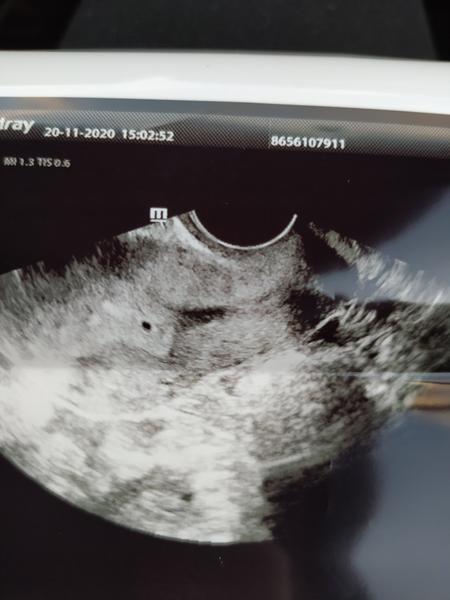

@sarah16 už je to potvrdené,malé zrniečko 2mm😌